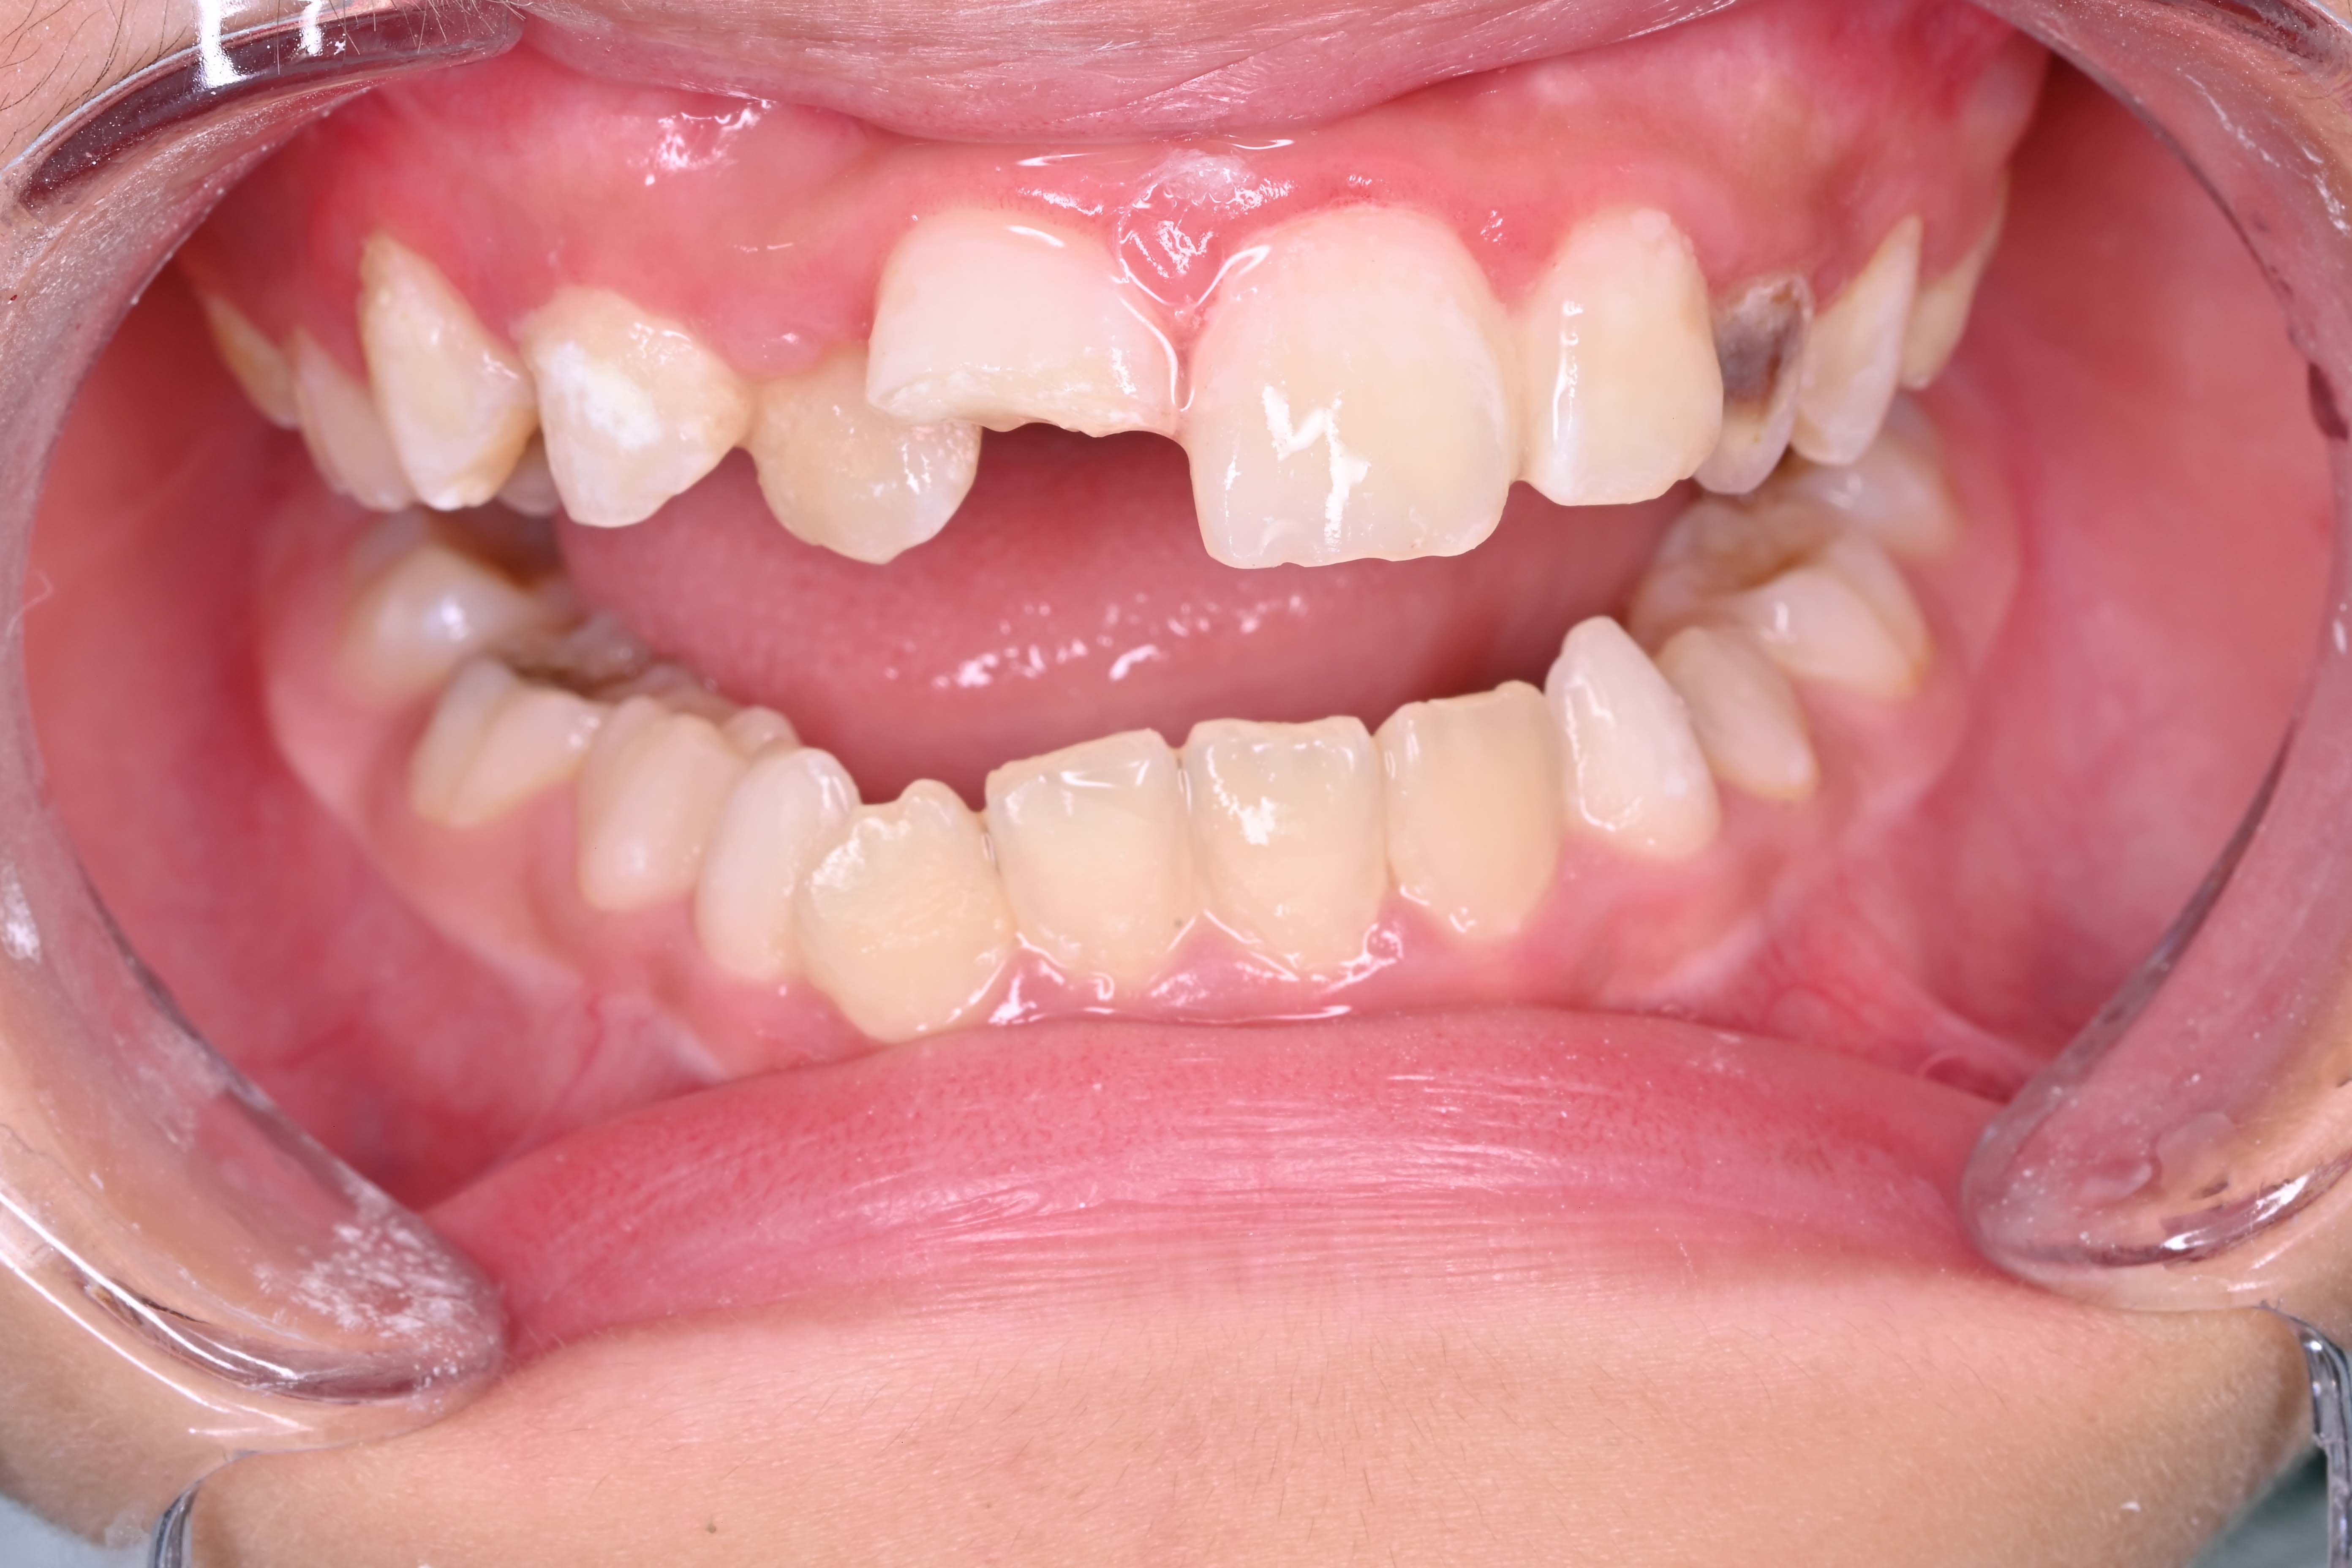

外伤折断树脂堆塑 - 案例一

术前 术前

术后 术后